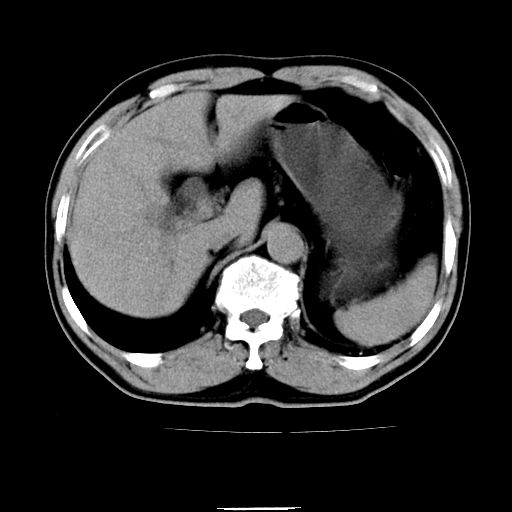

以下是引用chenqiong在2010-3-25 20:56:00的发言:[br]1、胆囊炎,胆囊息肉[br]2、肝内胆管及胆总管扩张,胆总管下端结石[br]3、十二指肠乳头旁憩室

以下是引用zxl51642在2010-3-26 10:47:00的发言:[br]胆囊炎,胆囊息肉,胆总管扩张,但未看到明显肿块,肝内胆管扩张不像恶性,炎性狭窄或阴性结石可能吧,建议mrcp,右肾小囊肿